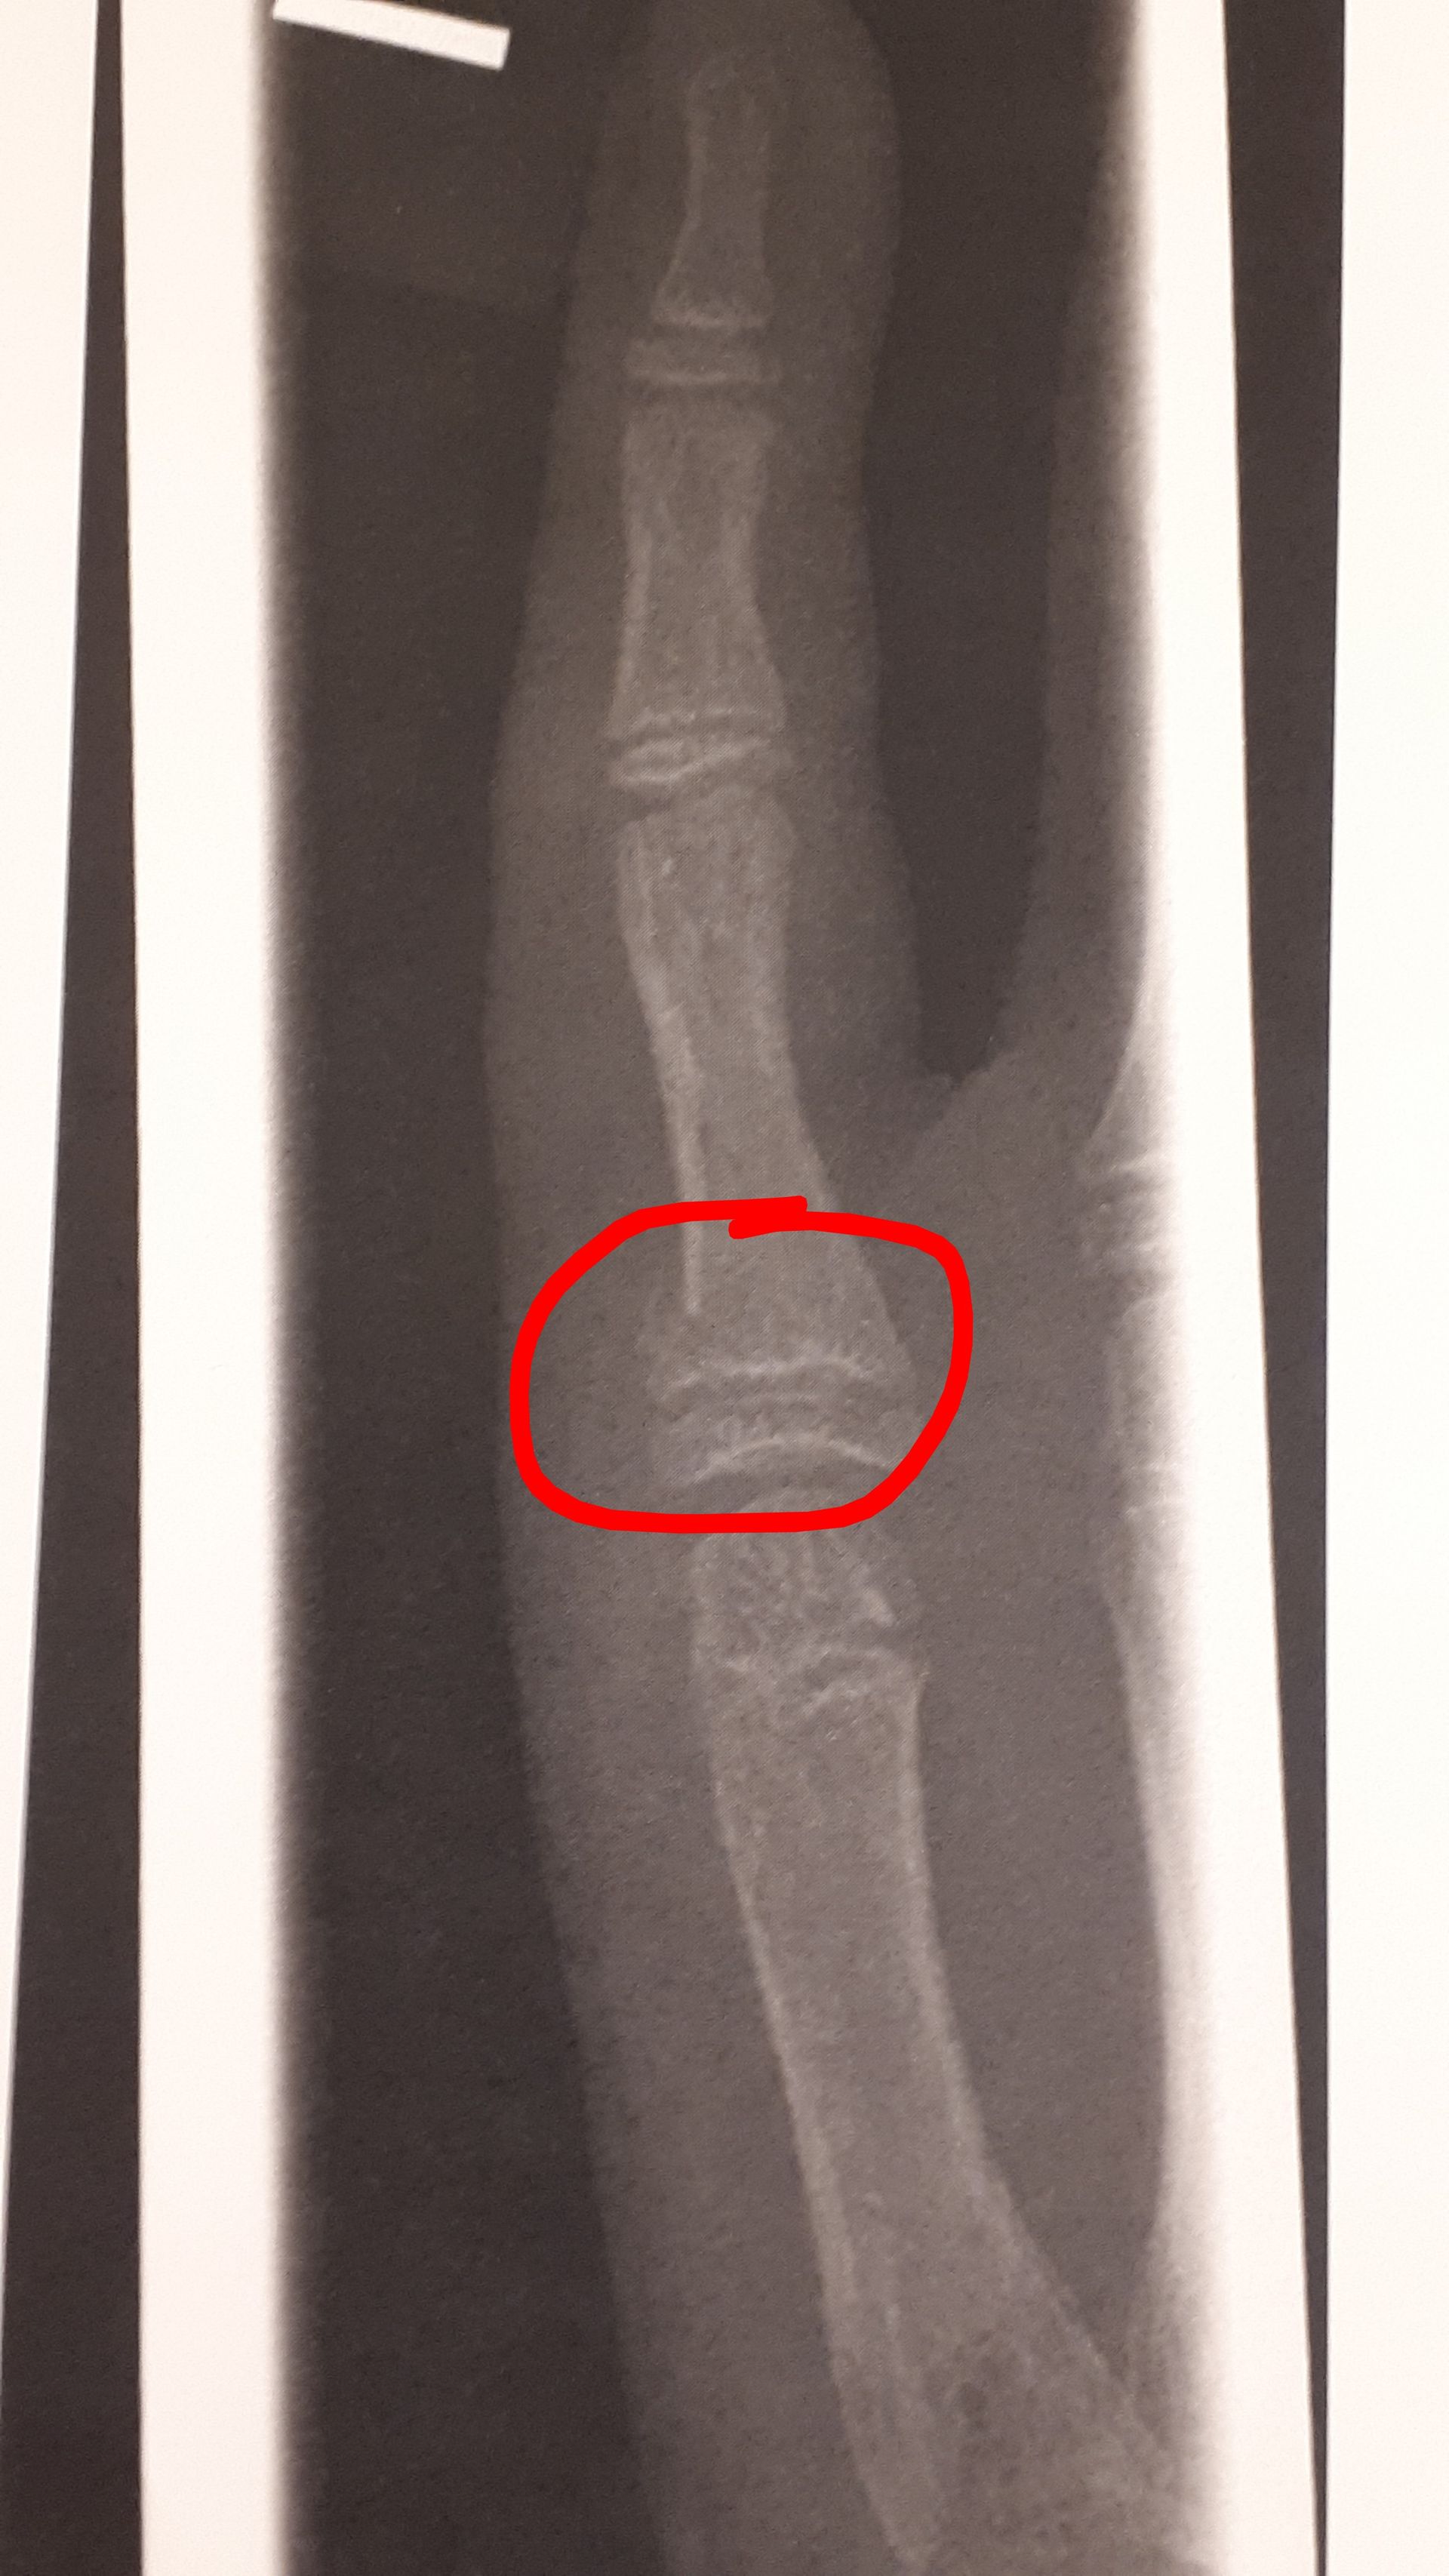

CactusCat14108 #gegenDatenschutz-Mannvor 3 MonatenAnonyman welcher Stelle genau?Ich schick gleich bearbeitetes bild mit rotem kreis

Anonymvor 3 MonatenCactusCat14108 #gegenDatenschutz-MannIch schick gleich bearbeitetes bild mit rotem kreisDanke

CactusCat14108 #gegenDatenschutz-Mannvor 3 MonatenKatze®️Am kleinen Finger OP haben die bei mir nd gemacht, lohnt nd sagten sieBei mir isser verdreht, und muss mit so 2 kleinen drähten befestigt werden

Anonymvor 3 MonatenCactusCat14108 #gegenDatenschutz-MannBildkomisch dass man es auf dem bild nicht erkennt, aber der arzt hat es erkannt

Anonymvor 3 MonatenAnonymkomisch dass man es auf dem bild nicht erkennt, aber der arzt hat es erkanntalso dass es gebrochen ist

Ich schick gleich bearbeitetes bild mit rotem kreis

Ist verdreht

Bei mir isser verdreht, und muss mit so 2 kleinen drähten befestigt werden

Und die drähte kommen unter die haut halt

komisch dass man es auf dem bild nicht erkennt, aber der arzt hat es erkannt

also dass es gebrochen ist